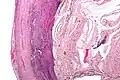

-

Micrograph of appendicitis and periappendicitis. H&E stain. -

Micrograph of appendicitis showing neutrophils in the muscularis propria. H&E stain. -

Acute suppurative appendicitis with perforation (at right). H&E stain.

Pathology diagnosis of appendicitis can be made by detecting a neutrophilic infiltrate of the muscularis propria.